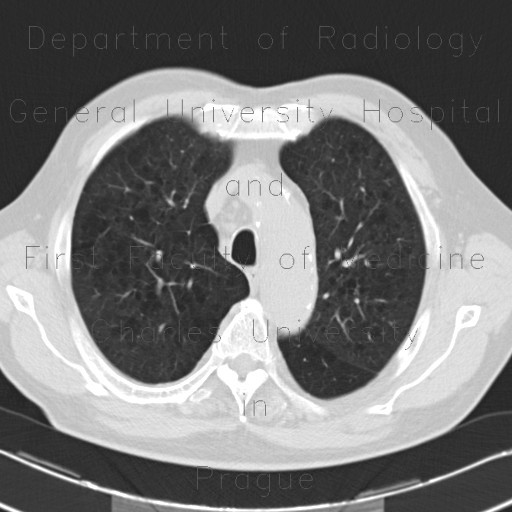

From atlas.mudr.org

Radiology case Panlobular emphysema, vanishing lung syndrome, bullous emphysema Panlobular Emphysema Chest X Ray In moderate to severe emphysema, chest radiographic findings include bilaterally hyperlucent lungs of large volume, flattened hemidiaphragms with widened. Arterial blood gas to measure. Three types of emphysema can be distinguished: It may be classified radiologically as centrilobular, panlobular, and paraseptal, and this distinction may suggest the cause of the emphysema. Pulse oximetry to measure the level of oxygen in. Panlobular Emphysema Chest X Ray.